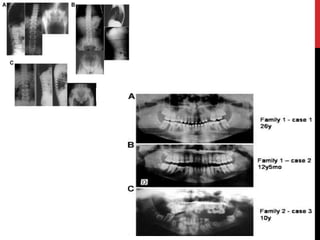

Amelogenesis imperfecta withtaurodontism (hypomaturation/hypoplastic AI)  Combination of enamel hypoplasia with hypomaturation.  Deciduous & permanent dentition involved.  2 patterns.

• #52 Amelogenesis imperfecta a syndrome in itself Clinically, a skeletal anterior open bite is seen in approximately 50% of patients with AI of either X-linked or autosomal inheritance. Such an association might be regarded as a syndrome but this does not appear as such in any classification. The significance of this common association has yet to be elucidated. Predominantly phenotypic classifications of AI have included a variant with taurodontism as an intrinsic feature – AI with taurodontism. This also goes beyond the strict definition of AI yet it is reasonable to include the condition in any classification of AI given that taurodontism is regarded as an ectodermal trait. The sheath of Hertwig, that maps the shape of the roots of teeth, is a derivative of the enamel organ and is also responsible for differentiation of the inner dental epithelial cells to ameloblasts producing enamel proteins. The subtle dentine changes reported by Winter et al. (1969) add further to our difficulties in understanding the complexities involved in some cases

• #53 Amelogenesis imperfecta in syndromes there are strong similarities between AIT and the tricho-dento-osseous (TDO) syndrome, which has the additional features of "curly hair" and skeletal changes including bone sclerosis. While the hair changes might represent a common ectodermal defect in TDO, the bony changes are more difficult to explain via a common pathway, as this assumes a mesodermal defect. TDO is caused by a mutation in the DLX3 gene [50]. One molecular study has reported that AIT and TDO are genetically distinct [51], whereas a later paper suggests that TDO and Amelogenesis imperfecta hypoplastic- hypomaturation with taurodontism (AIHHT) are allelic for DLX3 [52]. The literature records further examples of seemingly Ailike changes associated with other whole body findings, hitherto excluded from a diagnosis of AI. If we accept that AI may occur as an isolated trait, but also in association with a range of other abnormalities, then many different syndromes need to be considered in the differential diagnosis of patients with enamel defects. For further information regarding the full range of symptoms associated with AI, the reader is referred to Online Mendelian Inheritance in Man (For example see Kohlschutter syndrome, Platyspondyly with amelogenesis imperfecta, Amelogenesis imperfecta and nephrocalcinosis, cone rod dystrophy and amelogenesis imperfecta.